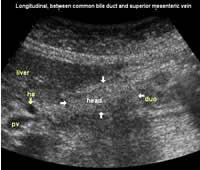

Longitudinal planes from right to left:

![]() Image22 |